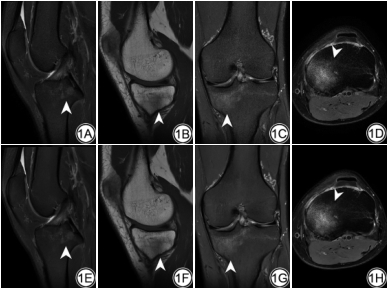

两名医师对FSEDL的图像整体质量、清晰度及诊断置信度的评分均高于FSEO,其中对FSEDL、FSEO的图像清晰度评分差异有统计学意义(P<0.05)。两名医师对图像质量主观评价的一致性ICC在0.710~0.898之间(表3)。图像质量客观评价:PDWIDL、T1WIDL图像上股骨外侧髁、股骨外侧髁软骨、滑膜液、髌下脂肪垫SNR明显高于PDWIO、T1WIO图像,同时PDWIDL图像上软骨/滑膜液CNR明显高于PDWIO图像,差异均有统计学意义(P<0.05)(表4、图1)。

两名医师分别基于膝关节2D FSEO及FSEDL图像对膝关节结构异常进行评估,κ值在0.954~1.000之间,P<0.05。同一名医师对FSEO图像和FSEDL图像的诊断结果比较,关于软骨缺损的检测和评估,诊断结果具有较好的一致性,κ值分别为0.769、0.771,P<0.05(表5、图3);关于半月板、韧带、骨髓及滑膜液的检测和评估,诊断结果具有极好的一致性,κ值在0.944~1.000之间,P<0.05(表5、图2~3)。